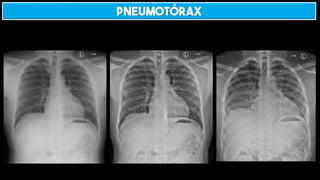

Pneumotórax

Pneumotórax hipertensivo